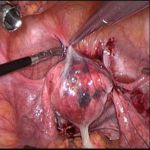

凡是来月经腹痛加上不孕不育的女性,一定要及时进行诊断和治疗。因为多来一次月经,腹痛就会加重一次,疾病也加重一次,所以越早治疗越好。最好的治疗办法就是在3D腹腔镜下把异位细胞凋零剂打入异位细胞使其死亡凋零。凋零剂如同除草剂撒在田地里,庄稼苗没问题,而异位病灶会消除掉,子宫的正常结构、正常组织细胞不受到伤害。